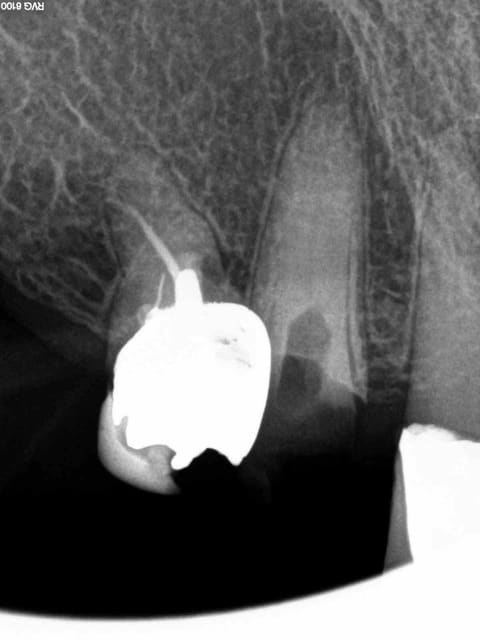

Arrivé un moment ou tu te dis que tu vas l'extraire, mais tu ne le fais pas parceque ca fait 3/4 d'heures que tu cherches ce putain de canal. Et enfin la lumière fut ( c'est le cas de le dire). -)))))

1 nfmvd7 - Eugenol

2 dvdqtt - Eugenol

3 f3ohf3 - Eugenol

4 zmohou - Eugenol

5 j0htr8 - Eugenol

6 e86kdq - Eugenol

7 fbttie - Eugenol